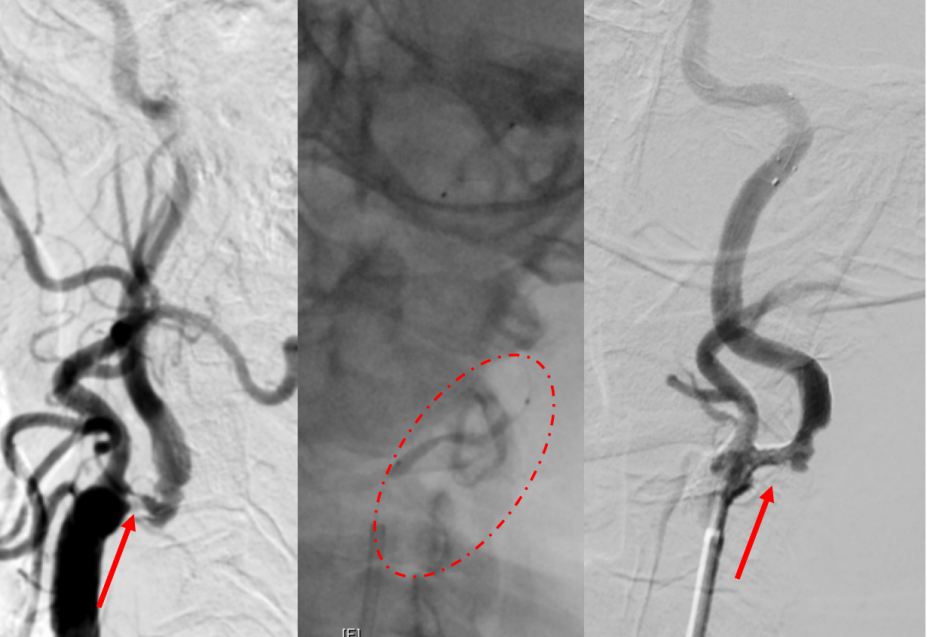

脑动脉造影:术前左侧颈内动脉血管极重度狭窄,管腔“发丝样”纤细,术中支架后血流明显改善

老赵听到自己的病情后,虽然内心很急,但失语的情况下又无法表达惊慌,眼神中透露出坚定的手术意愿,家人也快速地签署了手术同意书。作为手术的第一步,介入团队马上对老赵实施手术脑动脉造影明确病变,神经内科介入团队副主任医师付伟与主治医师王也给予急诊颈动脉支架植入治疗,术中两位医师小心地避开狭窄的斑块成分,将“保护伞”装置送过病变节段后,支架顺利植入真腔且无夹层,术中老赵就恢复了言语能力,术后12小时内恢复能够站立的肌力。入院1周后,老赵最终自己走着出了院。“感谢医院绿色通道,及时治疗才能让我这么快就恢复了!”老赵高兴地说。